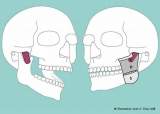

Sorpresa anatómica: descubrieron una tercera y súper profunda capa del músculo masetero

Lo novedosos de este hallazgo científico es que nunca se había identificado correctamente ese sector. Pero un reciente estudio de la Universidad de Basilea publicado en Annals of Anatomy reveló la existencia de esta nueva sección, que va desde la apófisis cigomática hasta la coronoides.